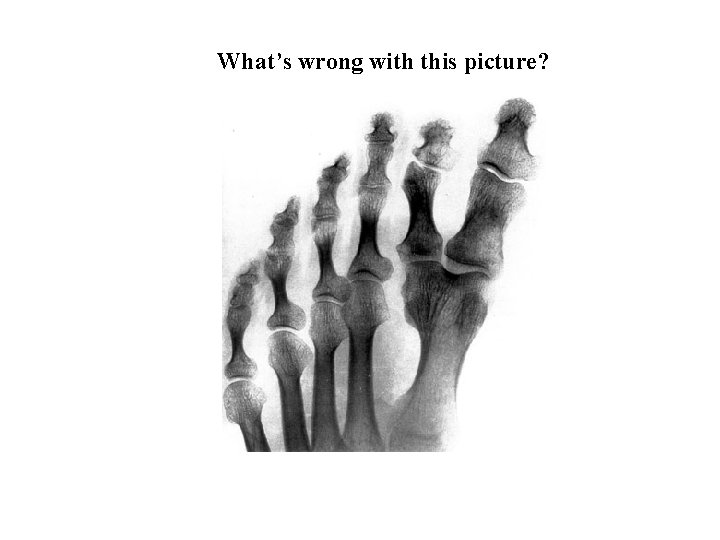

What’s wrong with this picture?